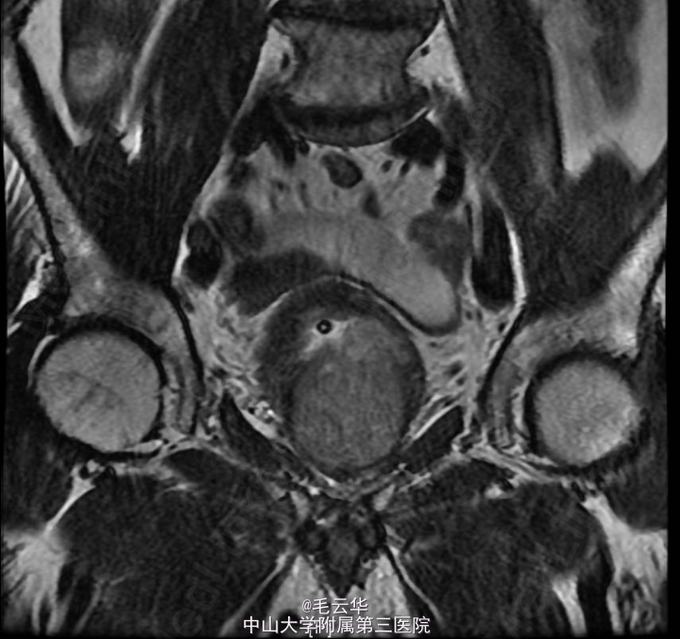

入院诊断:急性尿潴留,前列腺增生症 鉴别诊断:1.前列腺癌 2.膀胱颈纤维化 3尿道狭窄 4 神经源性膀胱 入院完善相关检查,盆腔MR示前列腺增生;左侧外周带T2WI信号降低,恶变待排,建议活检。B超引导下证实前列腺癌Gleason3+3=6分。行腹腔镜下前列腺癌根治术。术后病理示前列腺腺癌(Gleason评分:3+3=6分),闭孔淋巴结未见癌。